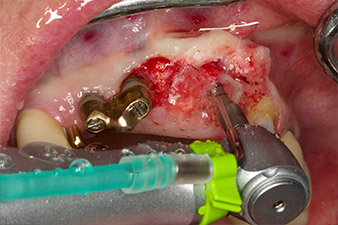

Motorized placement of the implant

Fig. 4: Motorized placement of the implant with the WS-75 L contra-angle handpiece at a ratio of 20:1 (programme P5).

In order to compensate for the periodontal bone loss and achieve an aesthetically pleasing result, the implantation was combined with guided bone regeneration (GBR) with xenogenic replacement material and a collagen membrane

(Fig. 5 and 6).

Xenogenic bone substitute material

Fig. 5: In order to achieve the best possible quality of peri-implant tissue, the site was additionally augmented with xenogenic bone replacement material and a collagen membrane in the scope of guided bone regeneration.